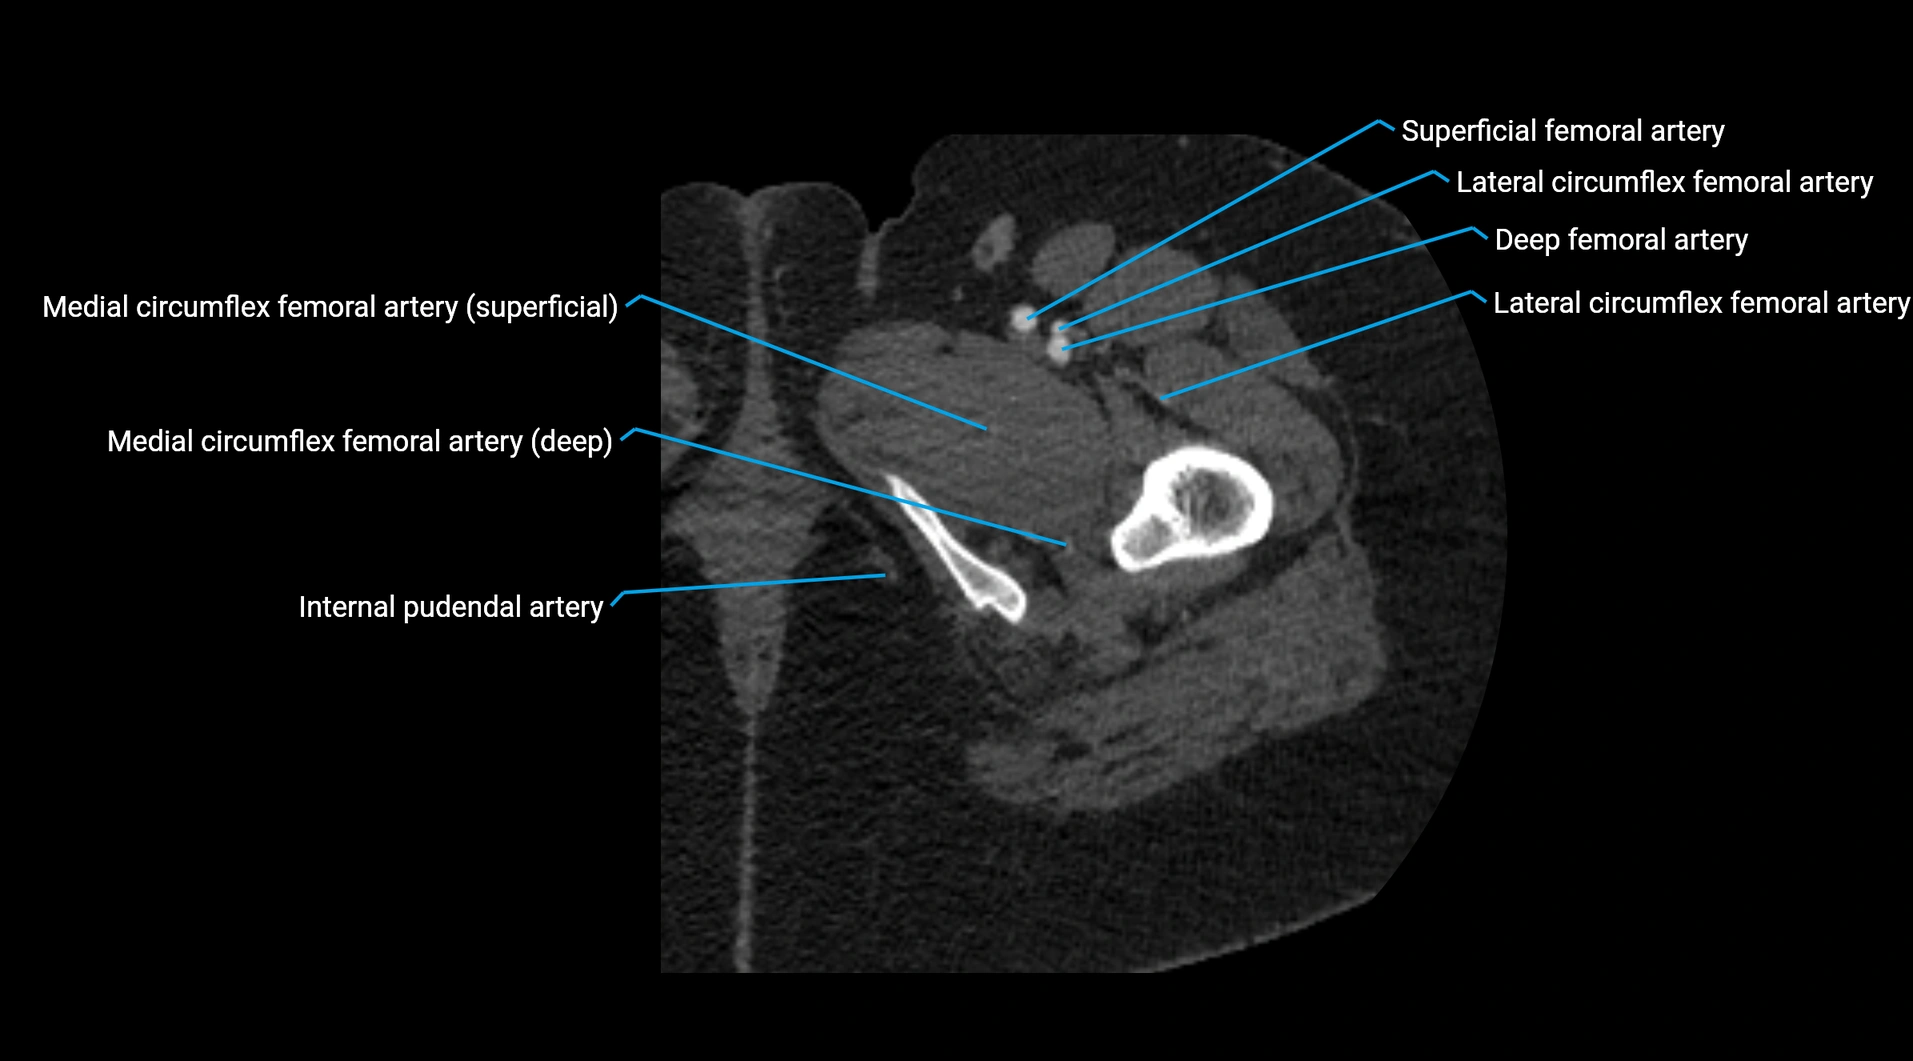

CT images

image